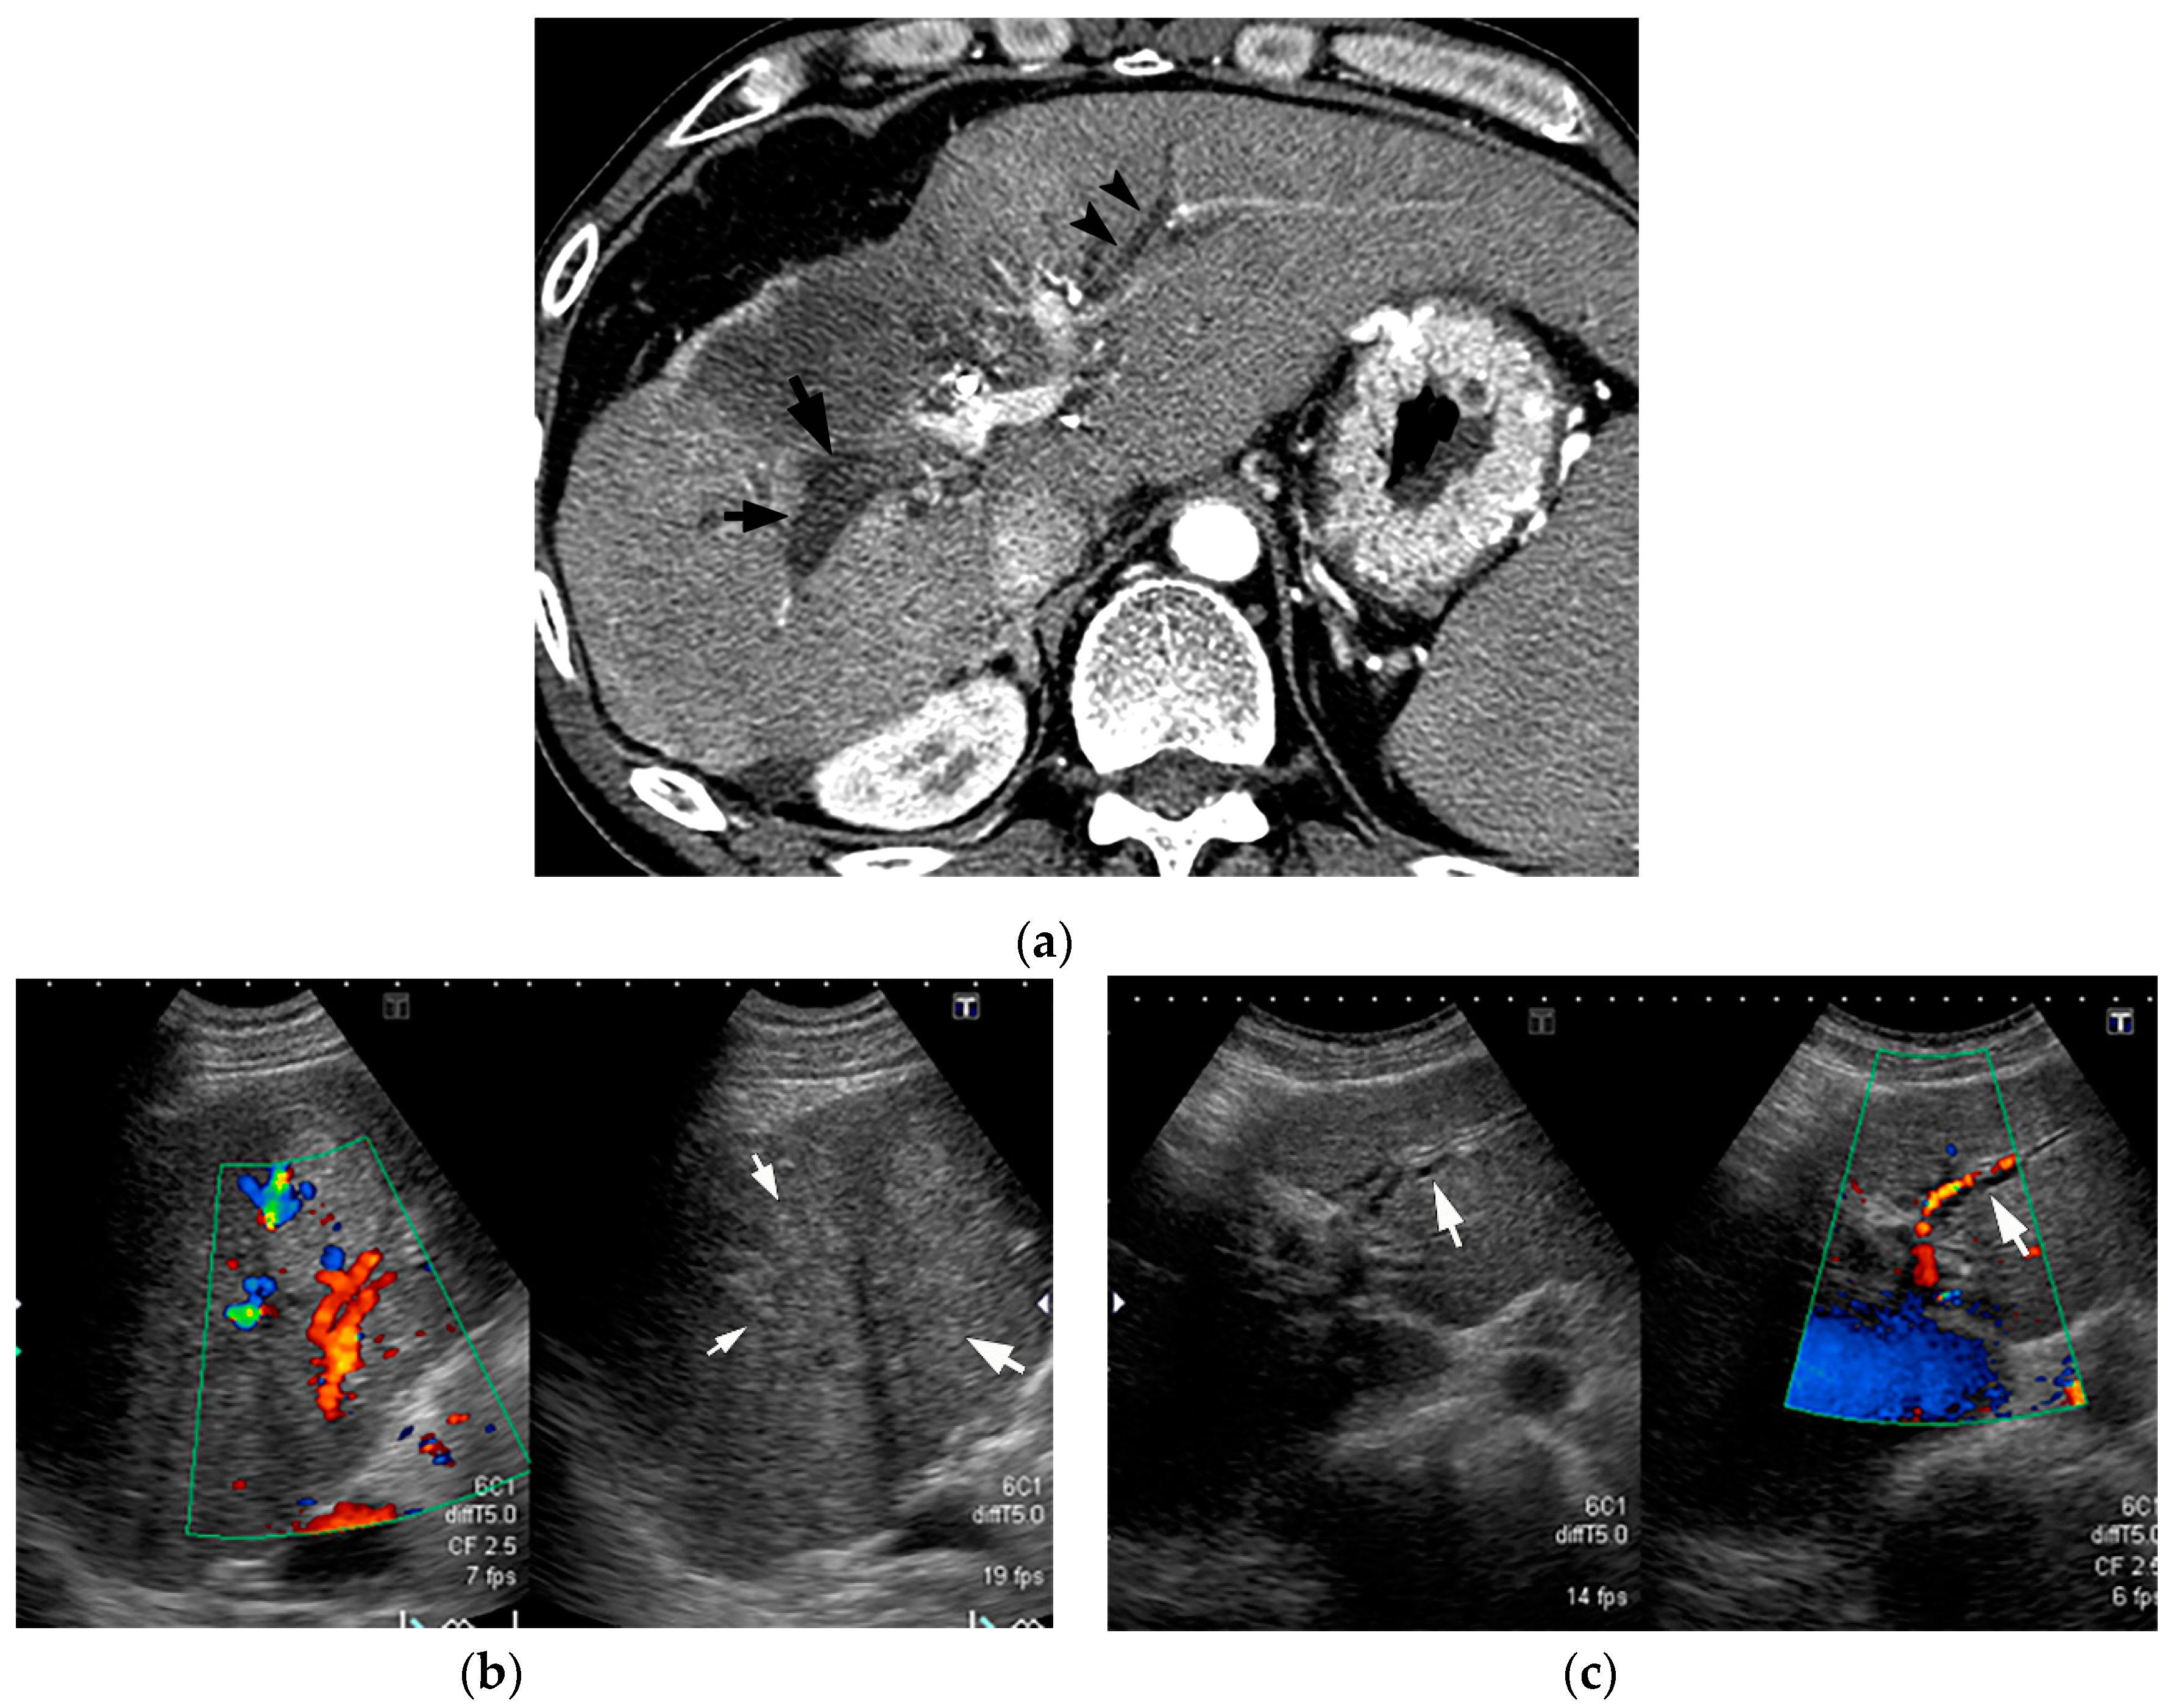

Figure 14. Comparison between CT and MR cholangiopancreatography (MRCP) findings of BDN. (a) On contrast-enhanced CT, a hypodense tubular structure is observed in the hilar area of the right liver lobe (arrow). Adjacent to this tubular structure, a large hypodense mass is observed in the medial segment of the liver (*). These structures are BDN (arrow) and a biloma (*). A dilated intrahepatic bile duct is also observed in the lateral segment of the liver (arrowheads). (b) On MRCP, although dilated intrahepatic bile ducts in the left lateral lobe of the liver are clearly observed, bile ducts in the hilar region and right hepatic lobe are unclear (arrow). Furthermore, the biloma in the medial segment of the liver is not clearly depicted on MRCP (*).

On T2-weighted MR images, BDN does not show marked high intensity, but slightly high intensity, which represents portal tract damage caused by imbibed bile salt, rather than a fluid-filled dilated bile duct (Figure 13). On MR cholangiopancreatography (MRCP), a necrotic portion of BDN shows variable signal intensities depending on the ratio of water to necrotic tissue (with/without hemorrhage) contents on heavy-T2 weighted images, which reflects the absence of intrahepatic bile duct dilation at the BDN site (Figure 14). Recognizing the difference between the T2-weighted MR images and CT findings provides confidence in making a diagnosis of BDN and not intrahepatic bile duct dilatation.